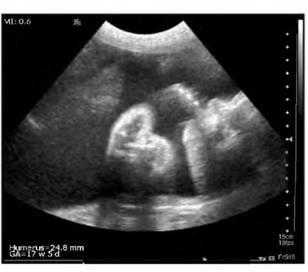

Плечевая кость = 16 мм - 14,5 нед. (рис. 3)

- ДБ (длина бедра) = 24 мм - 17 нед. (рис. 2)

Рис. 2. УЗИ плода - бедро.